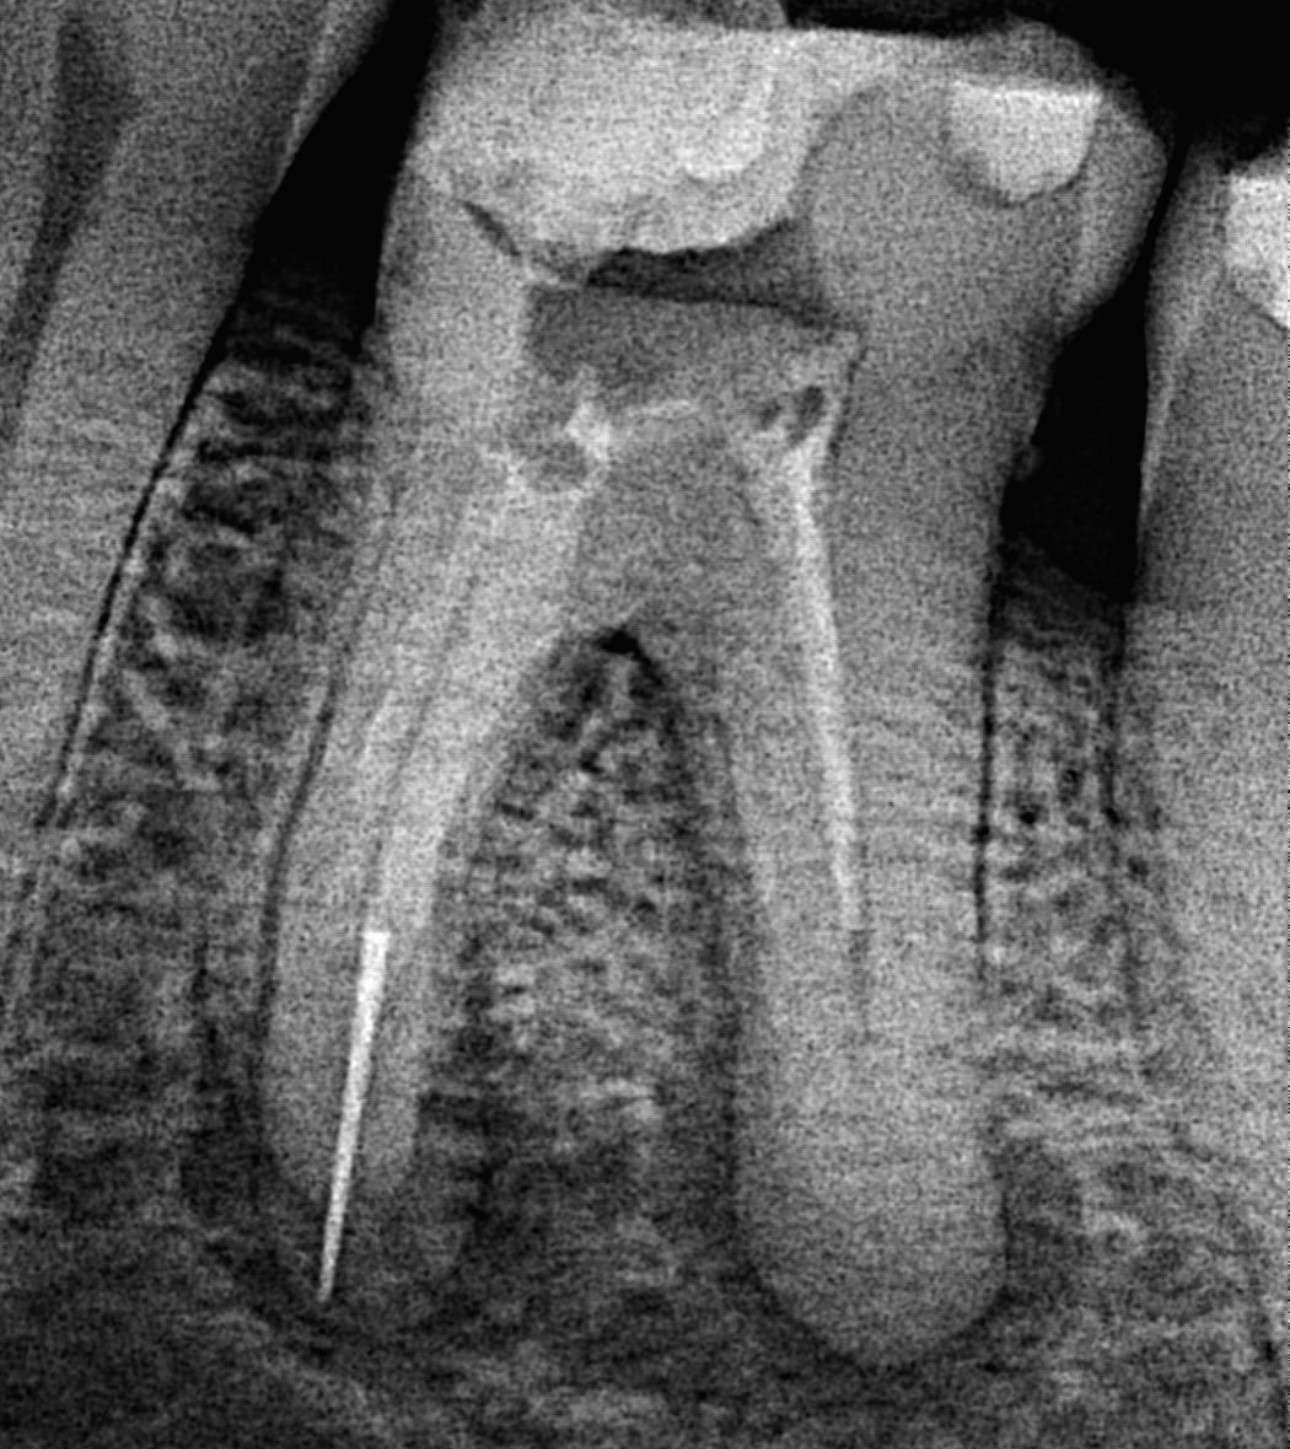

1. Evaluate the root canal treatment of tooth # 2.5?